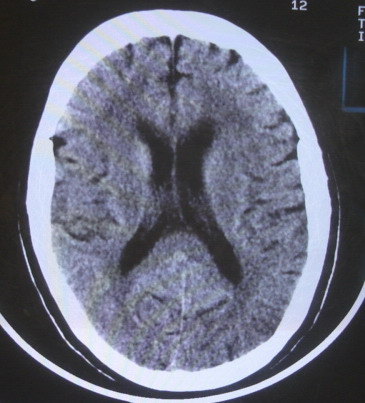

女  67岁 双下肢无力,行动不灵便

老年脑

脑萎缩,腔隙性脑梗塞.

双侧额桥束及左侧脑室旁多发腔梗塞+老年性脑改变

多发腔梗、老年性脑改变、脑白质异常。